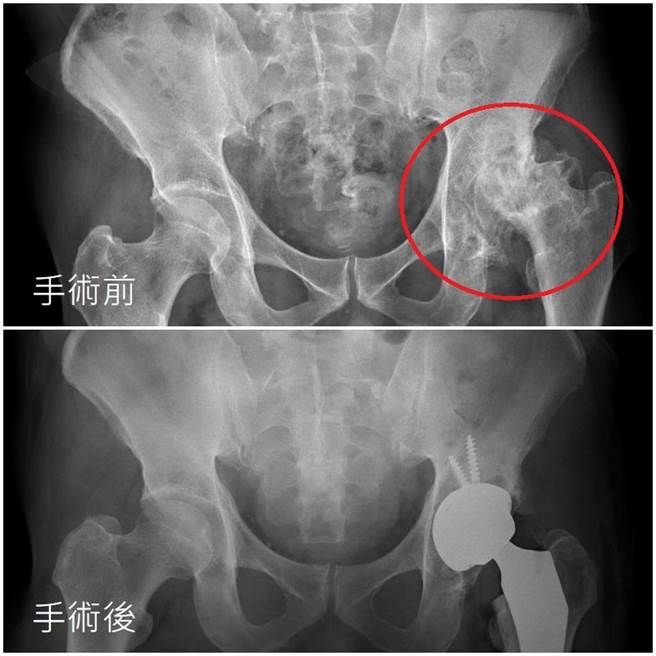

台中56岁林先生因长期喝酒应酬导致左侧「股骨头缺血性坏死」,幸经「全髋关节手术导引系统」置换人工髋关节顺利恢復。(亚大附医提供/潘虹恩台中传真)

林男就医时曾坦承长期抽菸、喝酒,年轻时并无异状,仅会偶尔闷痛,未料近1年来症状愈发严重,连爬楼梯都苦不堪言。黄揆洲说,林男于门诊检查时,髋部仅稍微内旋与外转,就让他痛到大叫;医疗团队建议林男置换人工髋关节,起初林男担心术后「长短脚」犹豫不决,接受手术后3天即顺利出院,1个月后就继续享受山林之乐。